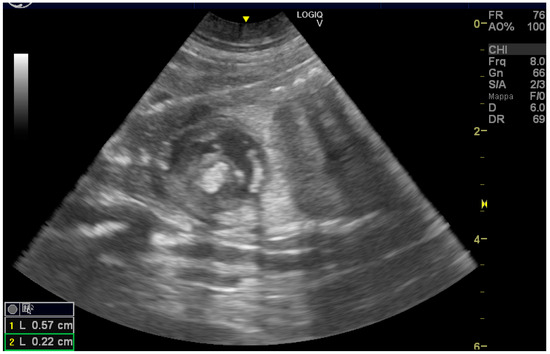

Ultrasound, Histomorphologic, and Immunohistochemical Analysis of a Cardiac Tumor with Increased Purkinje Cells Detected in a Canine Fetus 42 Days into Pregnancy

2. Case Description

2.1. Clinical Findings